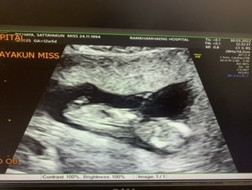

เราท้องได้9weekแต่ไปซาวกับไม่เจอตัวน้องคะซาวทั้งหน้าท้องและทางช่องคลอดตอนนี้เครียดมากการคัดเต้าก็ยังปกติคะมีเหม็นกลิ่นอาหารบ้างตอนนี้จิตตกเข้าออกตามเว็บหาข้อมูลทำใจไม่ได้เลยคะแม่ท่านไหนเป็นแบบนี้บ้างคะ

บ้านนี้ก็ท้อง 9 weekค่ะ ไปฝากตั้งแต่7week คุณแม่ลองให้หมอซาวน์ ช่องคลอดดูนะคะ เพราะหมอบอกถ้าซาวน์แบบหน้าท้องอาจจะไม่เจอ ซาวน์ช่องคลอดจะชัวร์กว่าค่ะ

ส่วนมาก9วีคต้องเห็นตัวน้องและหัวใจแล้วค่ะและการซาวช่องคลอดจะเห็นได้ชัดและแม่นยำที่สุดค่ะ แต่ถ้าคุณแม่ท้องลมจริงๆเดี๋ยวน้องก็กลับมาใหม่ค่ะ